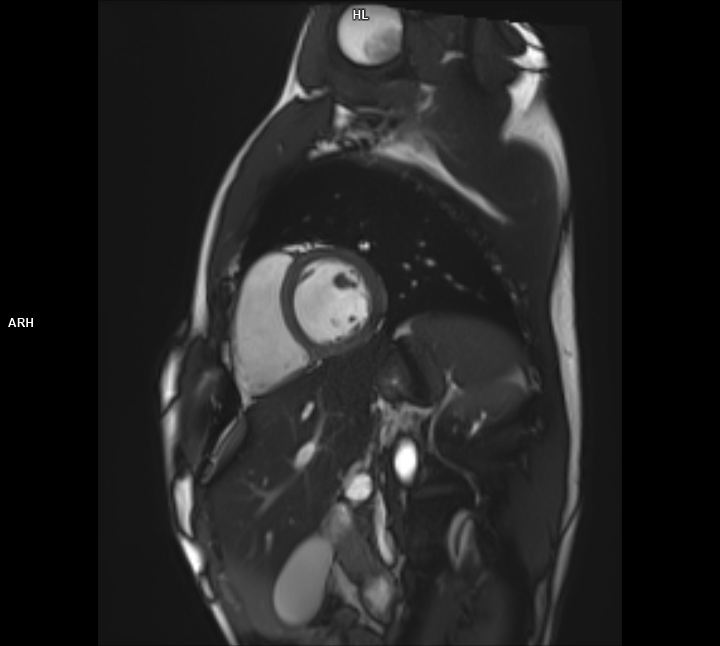

• Kardiyak MR

• 3 TESLA MR ÇEKİM GÖRÜNTÜLERİ

3 Tesla MR Çekim Görüntüleri

• 3 Tesla MR Çekim Görüntüleri